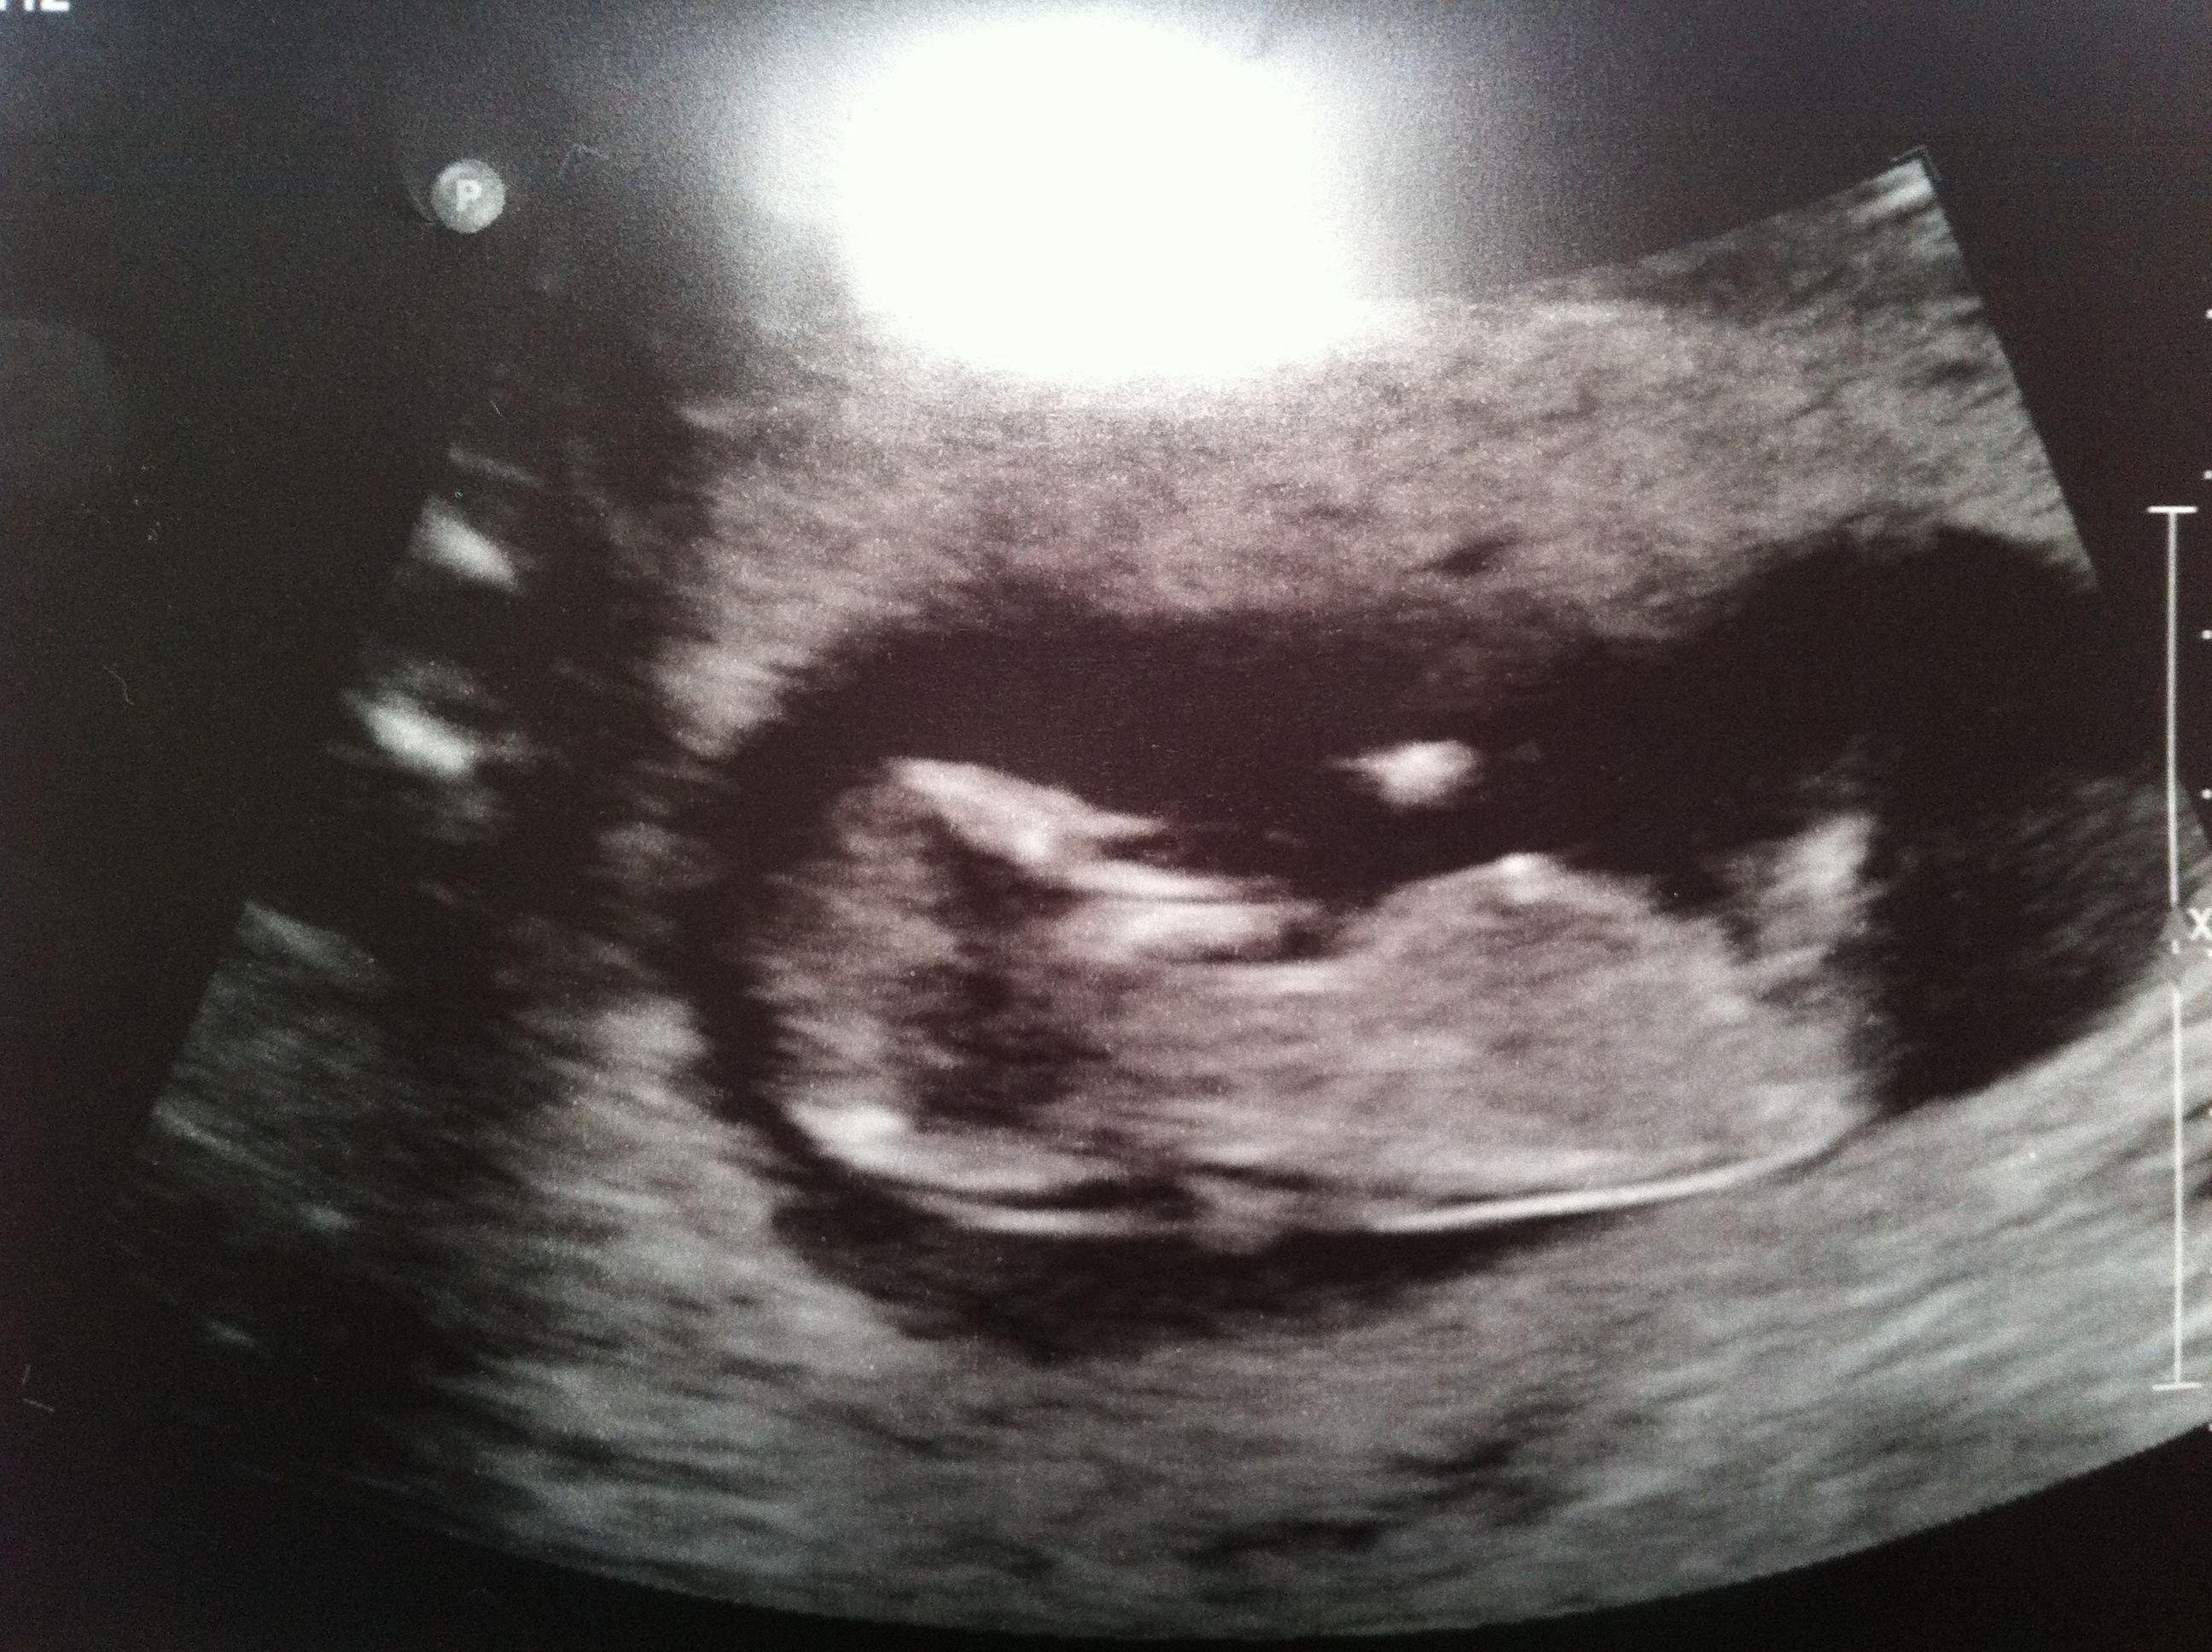

i had my scan today at 12w6d

i'm pretty sure i know what bub is but would love others opinions

we got terrible photos as bub was all over the place - one minute on my right, then on my left and all of a sudden flipped upside down. it just wouldnt stay still